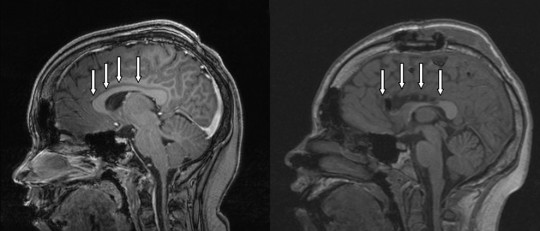

Durante su trayectoria, Eric Kandel ha estudiado la estructura celular del hipocampo y, a partir de ahí, ha propuesto teorías sobre la biología de la memoria. No sólo eso sino que, junto con los trabajos de Arvid Carlsson y Paul Greengard, quienes han explicado el mecanismo de acción de la dopamina y de otros neurotransmisores, Erik Kandel propuesto sistemas de acción molecular del aprendizaje y la memoria.

Los estudios de Kandel han sido realizados con distintas especies animales tanto vertebrados como invertebrados, y sus resultados han sido aplicados para la comprensión de los seres humanos. Kandel sugiere que la memoria está localizada en las sinapsis, con lo cual, cambios en la función de éstas son determinantes en la consolidación, la pérdida y la estructuración de la memoria, y en consecuencia del aprendizaje. Específicamente a través de esto se han estudiado alteraciones sinápticas a largo plazo así como posibles estrategias para revertirlas.